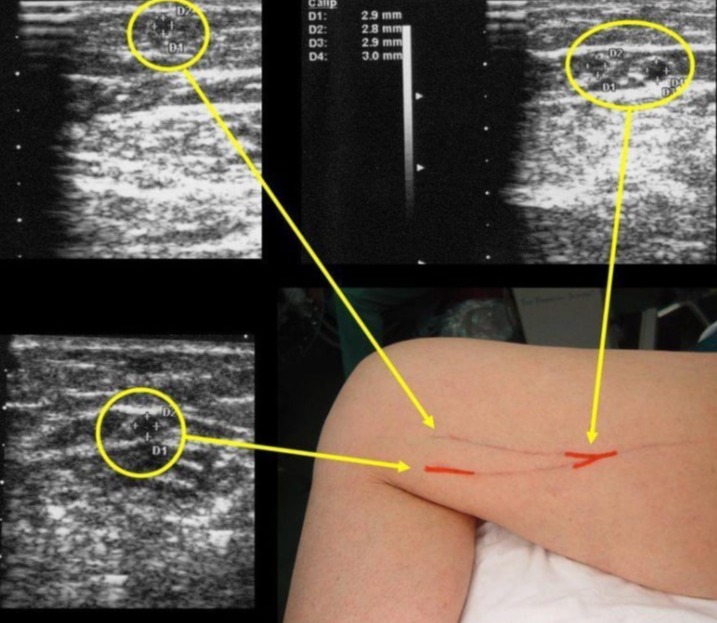

Doppler Αγγείων – Σφυροβραχιόνιος Αρτηριακός Δείκτης Πίεσης (ABPI)

Ο Δείκτης Πίεσης του Σφυροβραχιόνιου (Ankle-Brachial Pressure Index - ABPI) είναι ένα κλινικό μέτρο που χρησιμοποιεί τη μέθοδο του Doppler για να αξιολογήσει τον αρτηριακό παλμό και την πίεση του αίματος στις κάτω άκρες συγκριτικά με την πίεση του αίματος στον μπράχιο. Ο ABPI είναι χρήσιμος για την αξιολόγηση της περιφερικής αρτηριακής ανεπάρκειας.

Η διαδικασία περιλαμβάνει τα εξής βήματα:

Μέτρηση Πίεσης Σφυροβραχιόνιου (Brachial Pressure Measurement): Αρχικά, μετράται η πίεση του αίματος στον μπράχιο χρησιμοποιώντας ένα σφυγμομανόμετρο.

Μέτρηση Πίεσης στον Πηγάδιο (Ankle Pressure Measurement): Στη συνέχεια, με χρήση ενός Doppler ultrasound, ο ακροατήρας τοποθετείται στο πηγάδι (συνήθως στον μηριαίο ή τον αχίλλειο τένοντα), και μετράται η πίεση του αίματος.

Υπολογισμός του ABPI: Ο ABPI υπολογίζεται διαιρώντας την πίεση στον πηγάδι με την πίεση στον μπράχιο. Η φυσιολογική τιμή του ABPI είναι περίπου 1.0, όμως, σε περιπτώσεις περιφερικής αρτηριακής νόσου, μπορεί να είναι χαμηλότερη.

Ο χαμηλός ABPI υποδεικνύει πιθανή περιφερική αρτηριακή νόσο, η οποία μπορεί να οφείλεται σε στενώσεις ή αποκλεισμούς στις αρτηρίες των κάτω άκρων. Αυτή η μέθοδος συχνά χρησιμοποιείται στην κλινική πράξη για την αξιολόγηση της αρτηριακής λειτουργίας και τη διάγνωση περιφερικής αρτηριακής νόσου.